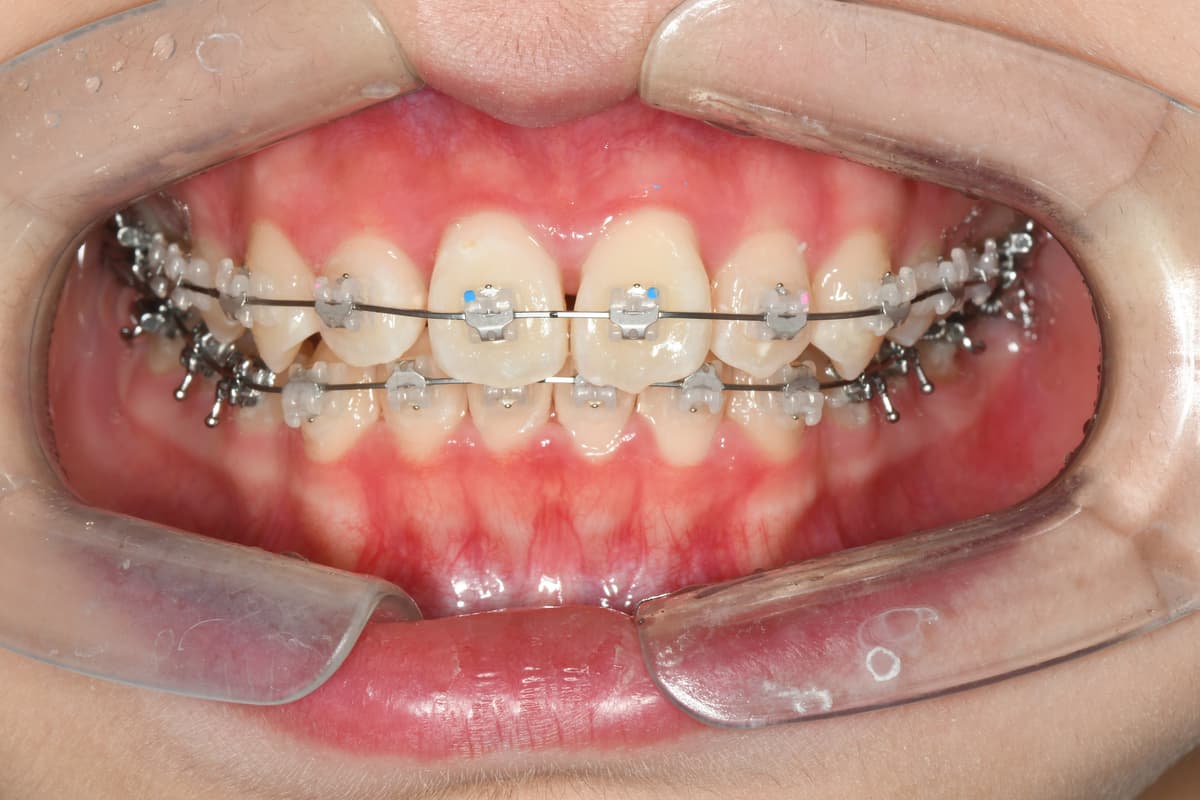

교정 치료 전후 사례

교정과 전문의가 직접 진료한

실제 환자 케이스입니다

이●● · 심한 부정교합